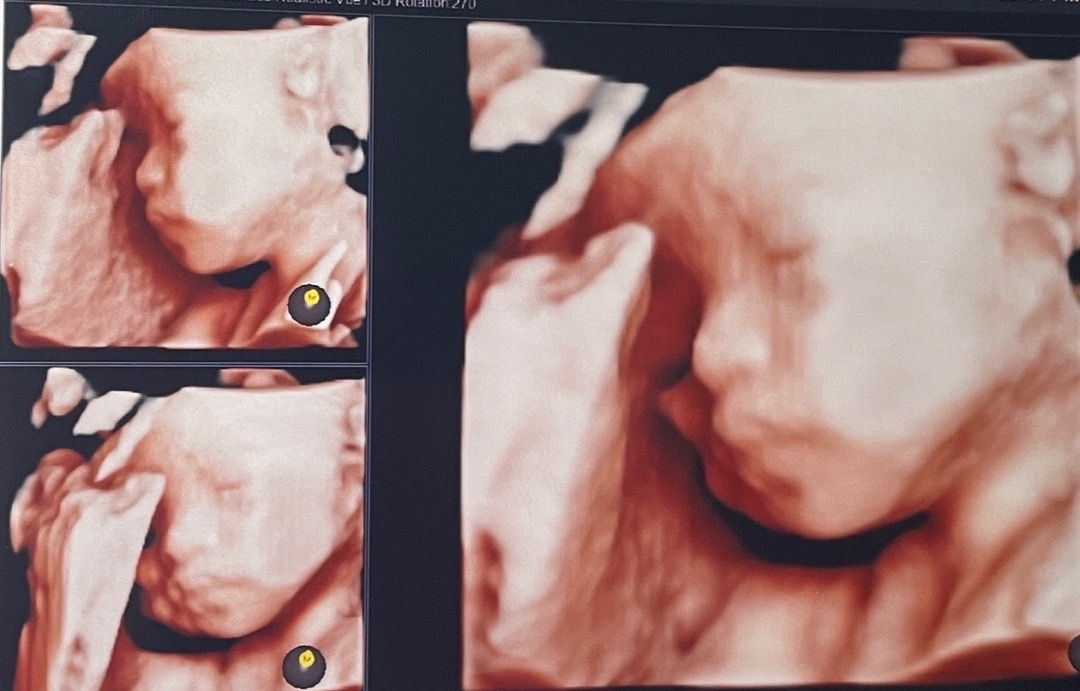

27주차 초음파찍었어요🙌

얼굴을 제대로 안보여줘서 조금 아쉽지만 그래도 잘 나온거 같네요🤗 건강하고 이쁘게 태어났음좋겠네요😍